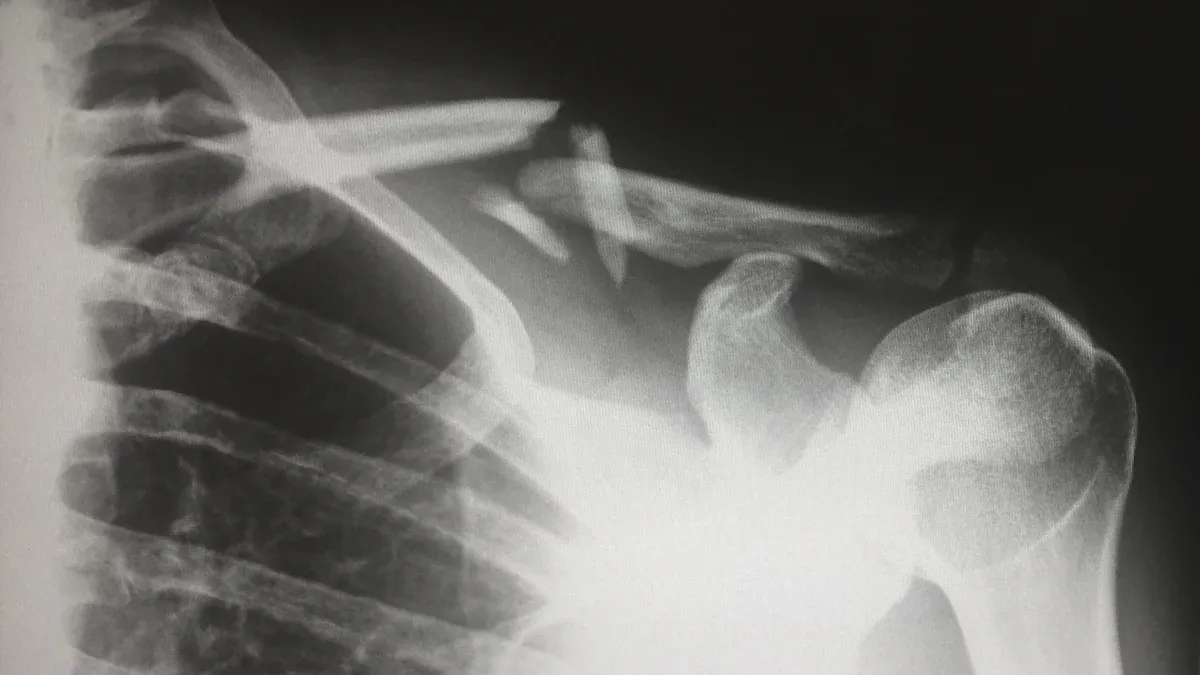

You will often see a locking plate used for complex fractures. Surgeons choose this plate when the bone is weak or the break is unstable. For example, doctors use a locking plate for a displaced fracture in the upper arm near the shoulder. This type of fracture happens a lot in older people. If the bone moves out of place, you need strong fixation. The locking plate gives you that stability. It holds the bone even if the bone is soft or has many pieces.

A locking plate works well for fractures in the hip, knee, or shoulder. You can use this plate for breaks that do not heal well with a cast. The locking plate helps keep the bone in the right position. It also works for bones with poor quality. You do not need the bone to be strong for the locking plate to work. The plate and screws lock together, so you get a fixed-angle construct. This means the plate does not move, and the screws stay tight.

Doctors use a locking plate for open fractures, where the skin breaks and the bone is at risk. You can also use this plate for fractures with many small pieces. The locking plate gives you better resistance to twisting and bending. You get more cycles before the plate fails. This means the plate lasts longer during healing.